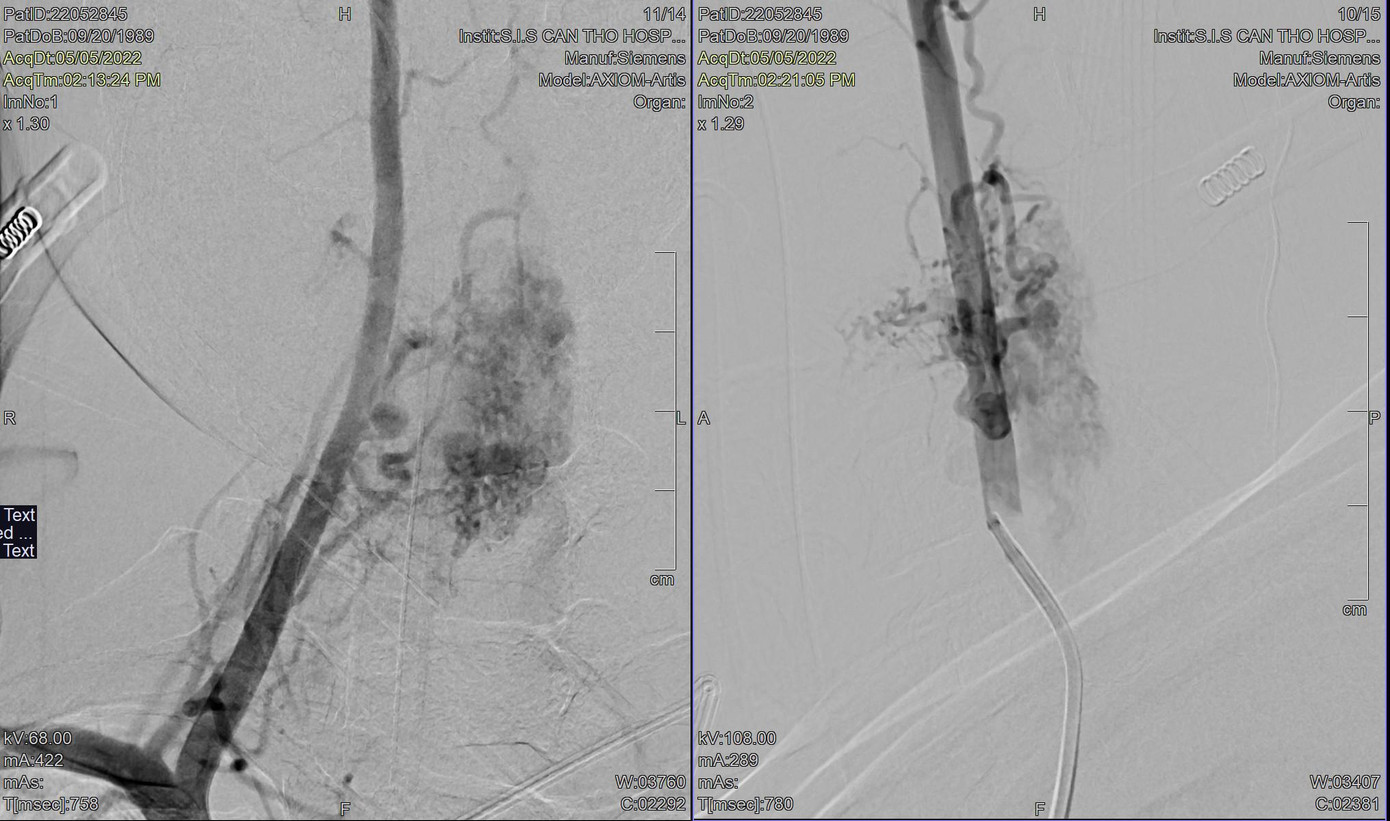

| Hình ảnh DSA cho thấy, bệnh nhân bị dị dạng mạch máu tủy cổ gây yếu liệt tứ chi |

Tại đây, kết quả chụp DSA cho thấy anh Đ. bị dị dạng mạch máu tủy vùng cổ ngang mức C5 -C7 cấp máu từ các nhánh tủy trước, tủy sau 2 bên và một nhánh của động mạch thân giáp cổ phải.

Qua hội chẩn, bác sĩ xác định người bệnh bị “dị dạng mạch máu tủy cổ bẩm sinh” rất nặng. Tình trạng dị dạng mạch máu phức tạp, không thể phẫu thuật hở, cách duy nhất là can thiệp nội mạch gây tắc mạch máu tủy dị dạng.